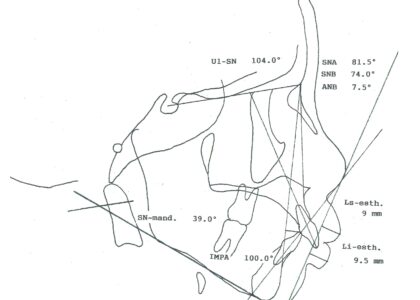

- セファロ